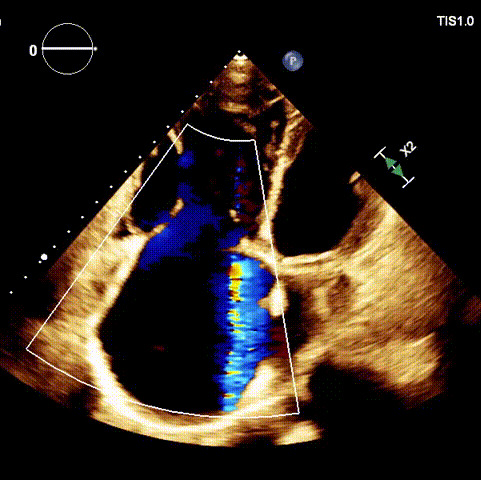

術(shù)前超聲

1.二尖瓣位機(jī)械瓣位置及功能未見異常;2.雙房及右室明顯擴(kuò)大(左房收縮容積115ml,右房收縮容積370ml,右室中段左右徑65mm,右室FAC37%),下腔靜脈及冠狀靜脈竇擴(kuò)張(下腔靜脈直徑44mm,冠狀靜脈竇直徑22mm);3.極重度三尖瓣反流(FTR 6+)。